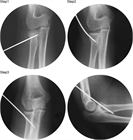

1. 橈骨頭骨折、橈骨頸部骨折の解剖学的特徴を把握する。

1. 橈骨頭骨折、橈骨頸部骨折は上腕骨小頭と橈骨頭が衝突して生じる。

1. 成人では橈骨頭に加え橈骨頚部も骨折しやすいが、小児では多くが橈骨頚部骨折である。